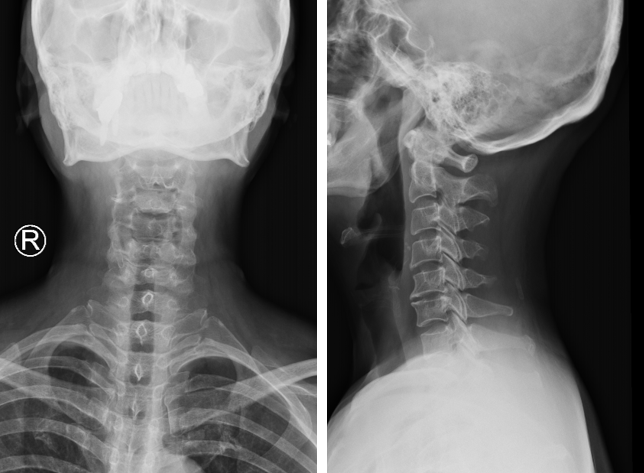

患者57歲女性,頸部劇痛伴右上肢外側(cè)放射痛至右手拇指食指,被動體位、右側(cè)屈頸體位,椎間孔擠壓試驗(+)、臂叢牽拉試驗(+),術(shù)前頸椎后凸,診斷為神經(jīng)根型頸椎病,行C5/6ACDF術(shù)式,術(shù)后患者疼痛顯著緩解,頸椎后凸顯著改善,這是由于頸椎間盤突出壓迫神經(jīng)根,頸椎代償性后凸使后方椎間孔空間增大,從而緩解神經(jīng)根壓迫。當手術(shù)解除神經(jīng)根壓迫后,原來頸椎的生理曲度就自然恢復(fù)了。圖1.術(shù)前頸椎X線,可見頸椎明顯后凸圖2.術(shù)前頸椎核磁,可見C5/6椎間盤突出,右側(cè)神經(jīng)根管狹窄圖3.X線顯示,術(shù)后頸椎后凸較術(shù)前顯著改善圖4.術(shù)后核磁顯示,C5/6椎間盤突出減壓徹底圖5.術(shù)前術(shù)后頸椎核磁矢狀面對比,減壓充分